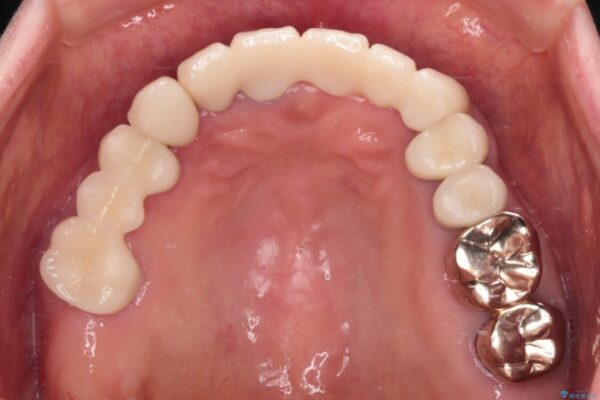

クラウンが不適合であったり、根管治療の必要なほどの痛みのある歯であったり、見た目の気になる前歯などをオールセラミッククラウンに補綴治療を行うこととしました。

処置を予定していた歯を仮歯に変えた時点で、下顎前歯の部分矯正を行うかどうかを尋ねたところ、折角なので行いたいと言うことでしたので、矯正治療を行うこととしました。

インプラント埋入や根管治療治療など、治癒に一定の期間を要する処置の合間に矯正治療を行うことで、効率的に治療を進めて行くことができました。

治療後

• 前歯をきれいにしたい インプラントや部分矯正を用いた総合歯科治療 治療後画像